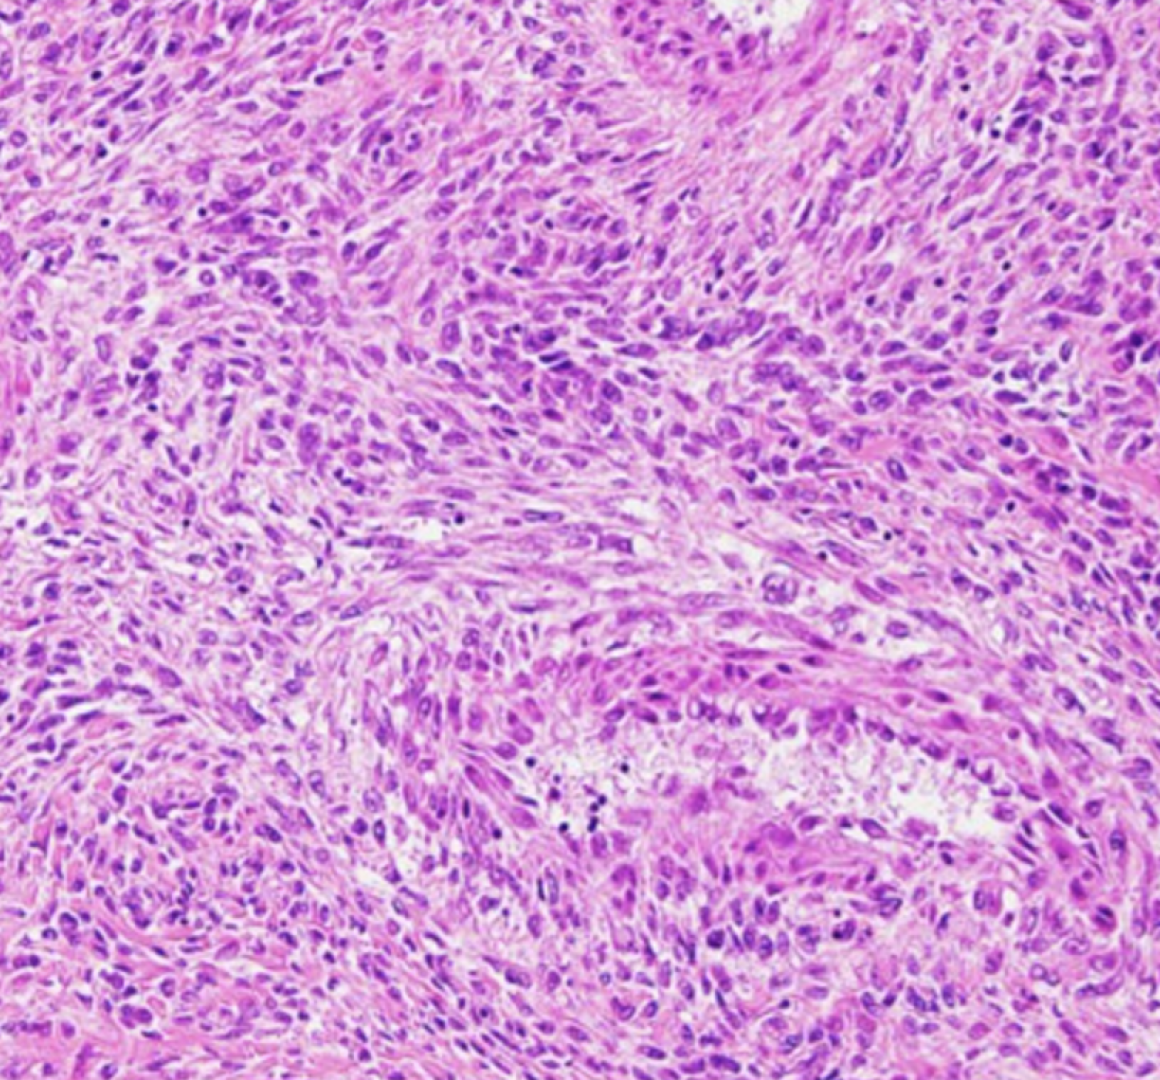

The pathology outreach program at Ochsner LSU Health Shreveport was established to unite an exceptional team of renal pathologists with advanced technology. Our team of fellowship-trained pathologists has more than forty years of combined experience and provide expert academic consultations on native and transplant renal biopsies. We are committed to providing the diagnostic support you need to ensure optimal results for your patients.

• Light Microscopy (LM): includes multiple sets of H&E, PAS, Jones Silver and Trichrome stains